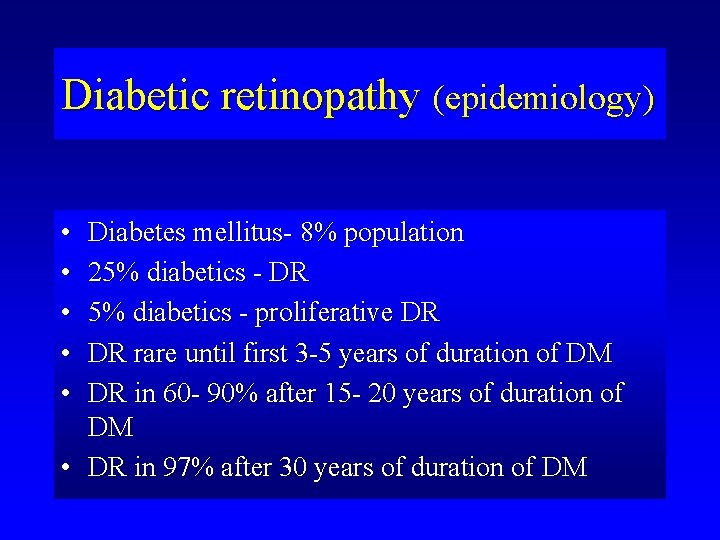

Diabetic retinopathy (epidemiology) • • • Diabetes mellitus- 8% population 25% diabetics - DR 5% diabetics - proliferative DR DR rare until first 3 -5 years of duration of DM DR in 60 - 90% after 15 - 20 years of duration of DM • DR in 97% after 30 years of duration of DM